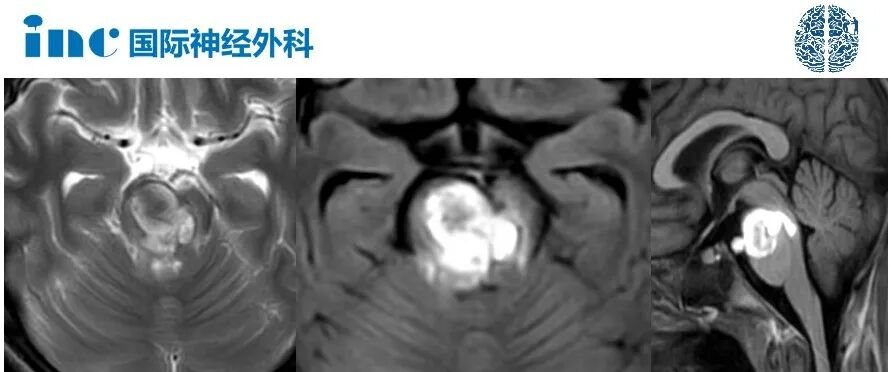

病情恶化速度超出预期,病因为脑干出血。颅脑CT检查显示患儿存在严重脑干海绵状血管瘤出血伴周围水肿。直至术前,患儿持续意识模糊、基本丧失肢体活动能力、吞咽功能障碍、饮水呛咳,需依赖鼻饲维持营养。

根据术前MRI检查,较大出血性病变位于桥脑腹侧上部,伴有周围内源性水肿。这表明病变严重且危险,与患儿临床症状相符。由于患儿存在吞咽困难,同时面临吸入性肺炎风险。